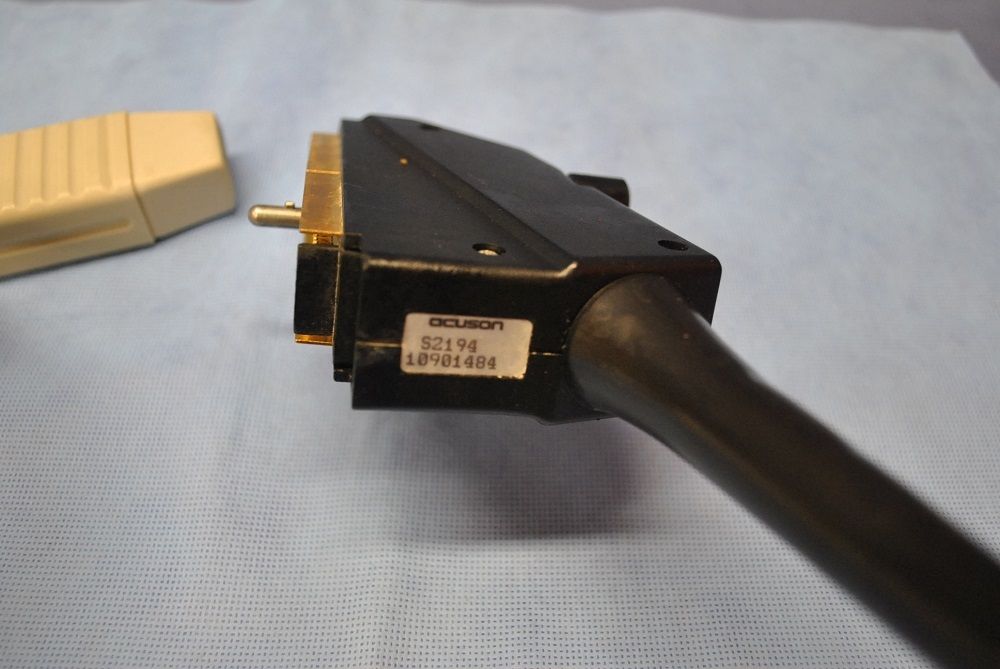

Acuson Linear Ultrasound Probe 7L3 08267217